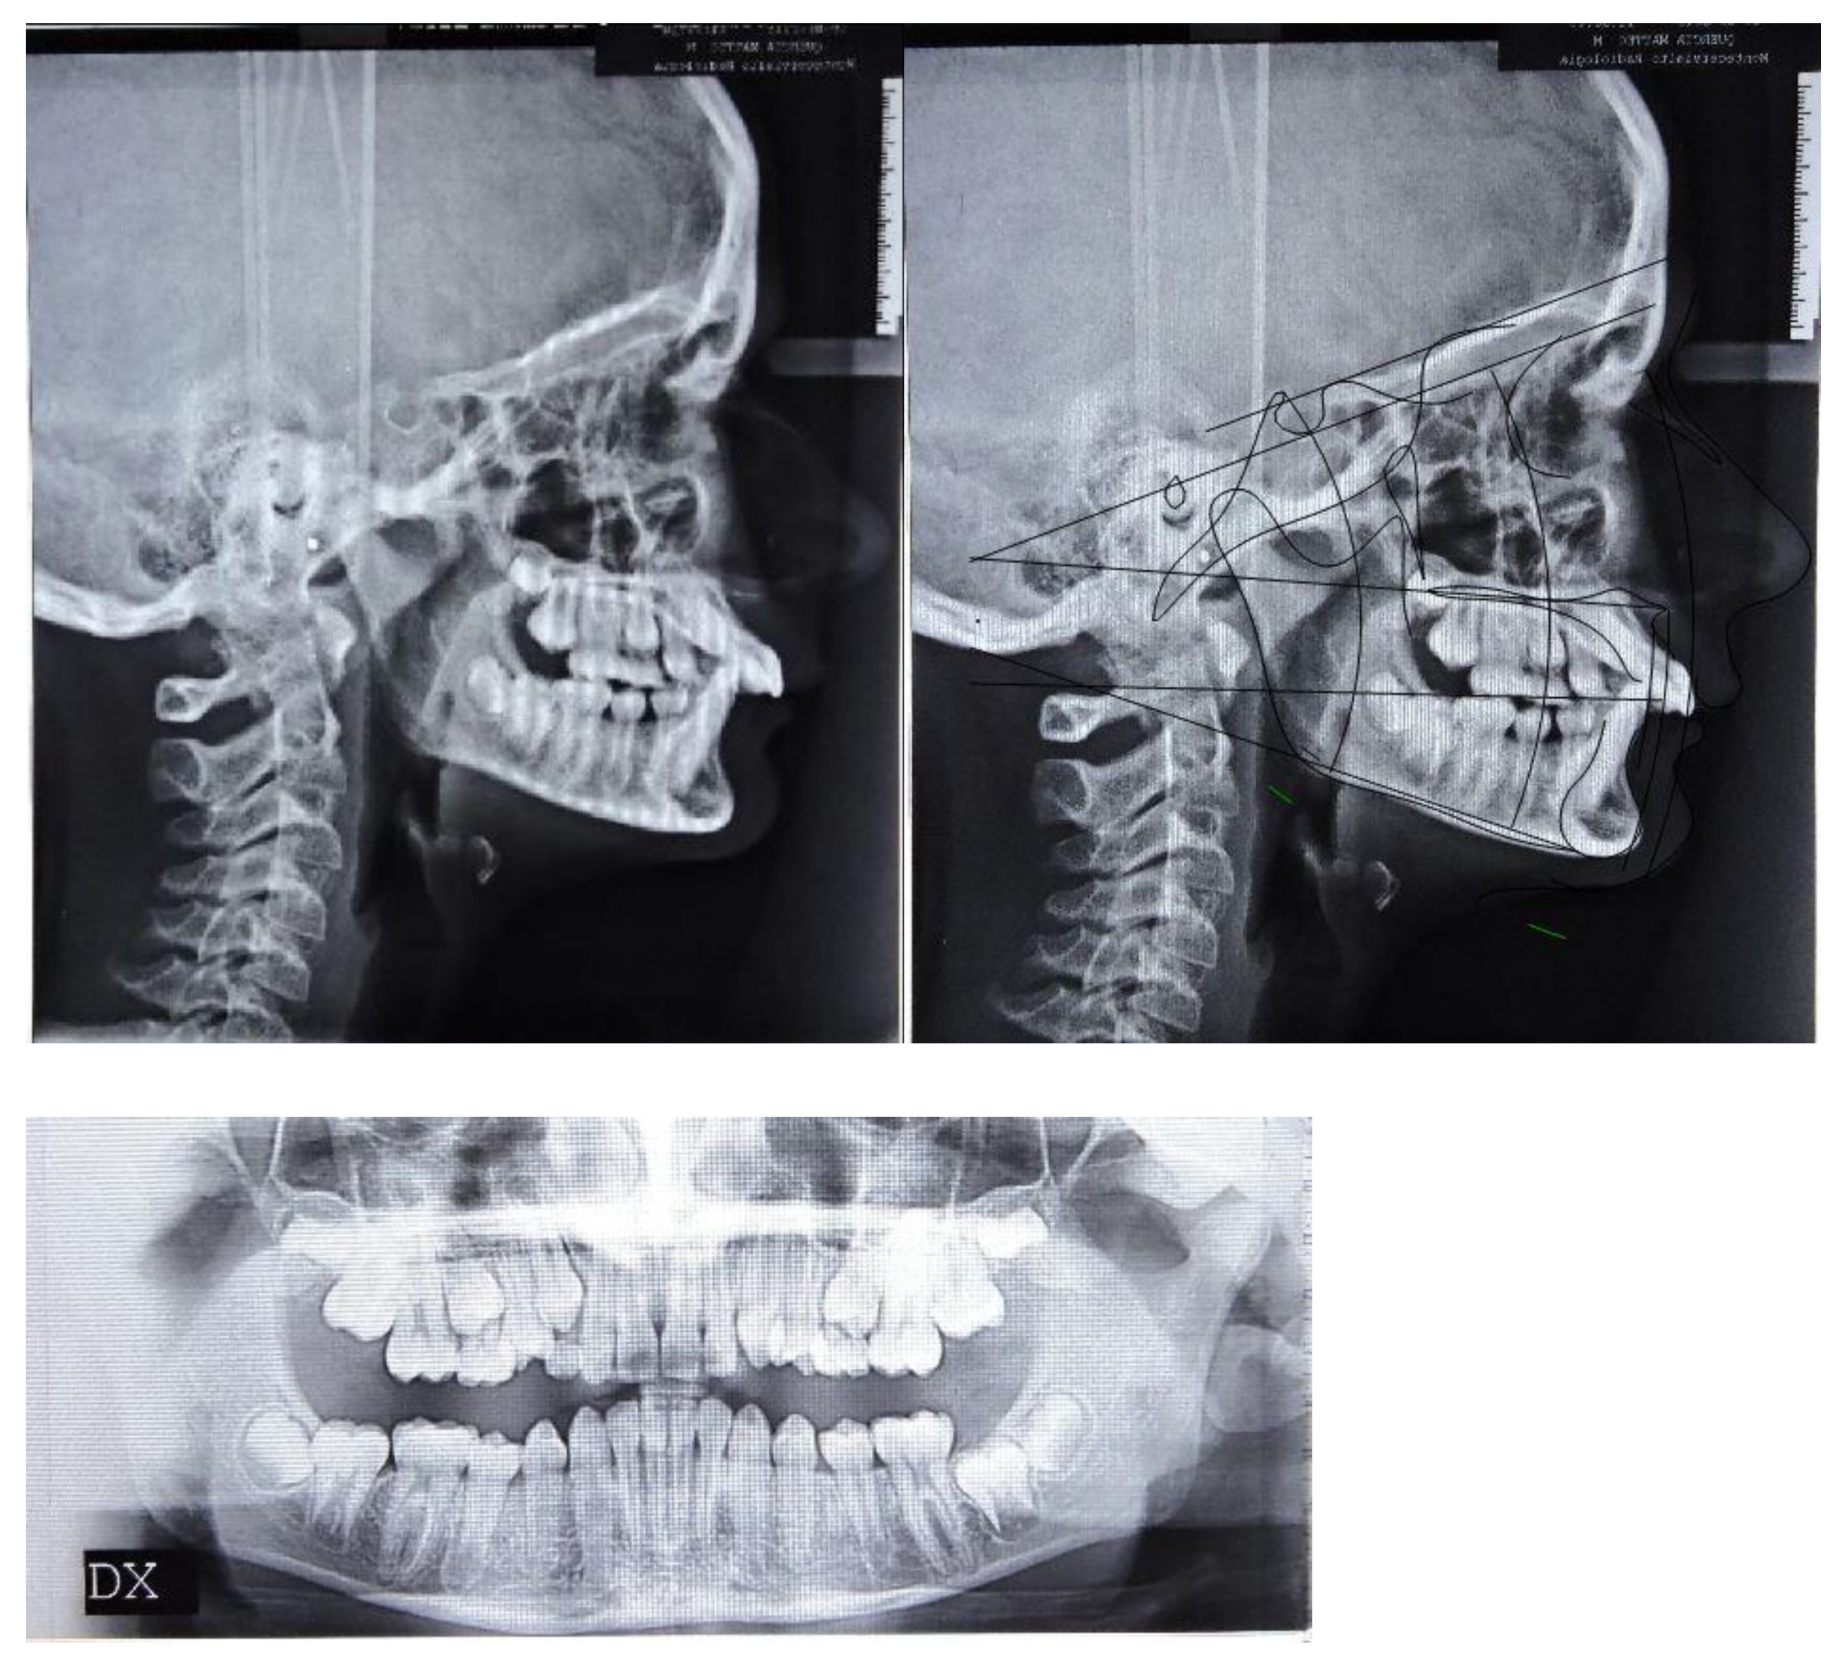

The patient was a 12.7-year-old Caucasian male with a chief complaint of excessive exposure of upper incisors (Figure 1). The general medical history was negative for illness, allergy. The patient did not present any familiarity for Angle Class II malocclusion and had not received any previous orthodontic treatment. Facial photographs revealed a convex profile with a hypodivergent growth pattern. At intraoral evaluation, the patient showed palatal impingement of the mandibular incisors on the palatal mucosa, as well as mandibular lip interposition between upper and mandibular incisors; narrow upper and mandibular arches (maxillary intermolar width-distance between maxillary first molar palatal cusp tips: 43 mm; mandibular intermolar width-distance between the central fossa of mandibular first molars: 46 mm), a bilateral molar and canine Angle Class II relationship, increased overjet and overbite with a deep curve of Spee were observed (Figure 1).

Figure 1.

Pre-treatment intraoral, extraoral photographs and radiographic examination.

In accordance with the Radiographic Guidelines of the British Orthodontic Society (last access: 1 March 2021, https://www.bos.org.uk), lateral cephalometric radiographs were obtained and analyzed. Landmarks and measurements were validated by Shaw et al. [4], and all data were anonymized.

The orthopantomography revealed a late mixed dentition, with the absence of “tooth developmental anomalies” of number, size, shape, eruption, position, structure.

According to Steiner’s cephalometric analysis [5], the patient showed a skeletal Class II relationship (ANB = 6°; Wits = 4 mm). Referring to the anterior cranial base (SN plane: Sella-Nasion), the patient presented a retruded mandible (SNB = 75°) with an increased inclination of upper incisors (U1-SN = 125°; IMPA = 90°) (Figure 1). The overjet and the overbite were also increased at the beginning of treatment (overjet = 8 mm; overbite = 6 mm) (Figure 1).

According to the Sassuoni analysis of vertical facial proportions [6], the patient revealed a skeletal deep bite tendency as the anterior cranial base plane, the Frankfort plane (FH), the palatal plane and the mandibular plane tended to converge far behind the face. However, the mandibular plane and the occlusal plane intersected relatively close to the face, owing to a deep curve of Spee with extrusion of mandibular incisors. (Figure 1). According to Steiner’s cephalometric analysis, it was confirmed that the occlusal plane (OP) was almost parallel to Frankfort’s plane (OP-FH = 2°), and that the maxilla (palatal plane, ANS/PNS) was properly inclined with respect to Frankfort’s plane (ANS/PNS-FH = 4°); moreover, the angle (FMA) between mandibular plane (ML) and Frankfort’s plane (FH) revealed a forward rotation of the mandible at the beginning of the treatment (FMA = 19°).

According to the cervical vertebral maturation method [7], the patient was in a pubertal phase without completing his craniofacial growth (between CS2 and CS3) (Figure 1).